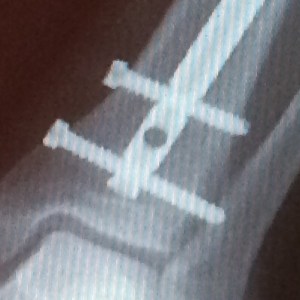

In 2016, Jeffrey pedaled us 1400 miles from Chicago to Albuquerque despite four irritating screws.

Two of the screws removed after the 2016 Ride. The rod remains.